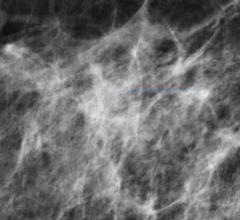

Despite decades of progress in breast imaging, one challenge continues to test even the most skilled radiologists ...

The Athena Breast Health Network has chosen Massachusetts-based Mammosphere to provide network management of medical images and associated clinical information required to conduct the WISDOM Study, a study involving more than 100,000 women that will help determine the optimal frequency and method of breast cancer screening.

Philips and Hologic, Inc. announced a global partnership agreement to offer care professionals integrated solutions comprising diagnostic imaging modalities, advanced informatics and services for screening, diagnosis and treatment of women across the world. The collaboration combines Hologic's innovative mammography technologies and Philips' leading portfolio of ultrasound, MRI, CT and X-ray systems, advanced informatics and broad range of services, including maintenance, upgrade, training and operational performance management services.

Fujifilm Medical Systems U.S.A. Inc. announced nine of the initial healthcare systems across the United States that have selected its Aspire Cristalle mammography system with 3-D digital breast tomosynthesis (DBT) option to improve their diagnostic imaging capabilities and women’s health patient outcomes.

Fujifilm details its latest innovations in women's health including its ASPIRE Cristalle mammography system with digital breast tomosynthesis software option and its Synapse 5 PACS and VNA, enabling secure, easy-to-manage storage and access to the complete patient imaging record throughout the healthcare enterprise.